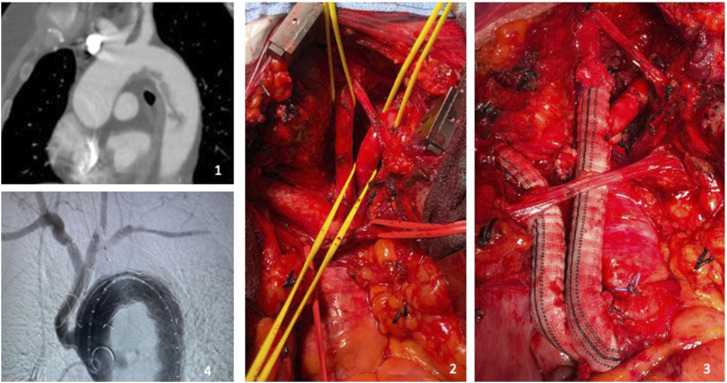

ObjectivesWe present two clinical cases of association between symptomatic free-floating thrombus (FFT) in thoracic aorta and rheumatoid arthritis (RA).MethodsIn the first patient, we observed a recent onset of peripheral and visceral signs of embolization: after a first treatment with anticoagulation, our Aortic team scheduled the coverage of FFT (sited in zone 1 of the aortic arch) with an anatomical debranching of anonymous trunk and left carotid artery, a left carotid-subclavian bypass, and a TEVAR of the aortic arch with proximal landing in zone 0 of the arch. The second case was characterized by chest pain, left upper limb ischemia, and CTA evidence of an FFT in zone 3 of the aortic arch; we planned a chimney-TEVAR on the left subclavian artery and descending thoracic aorta (with proximal landing in zone 2 of the aortic arch) to exclude the FFT.ResultsNo complications resulted and no new embolic episodes were registered.ConclusionsEvaluating the aorta is warranted in all patients with peripheral emboli of uncertain pathogenesis. In our opinion, the endovascular treatment of a symptomatic FFT could represent an effective and safe solution in a patient fit for endovascular surgery, but larger studies are required to define a personalized treatment strategy.